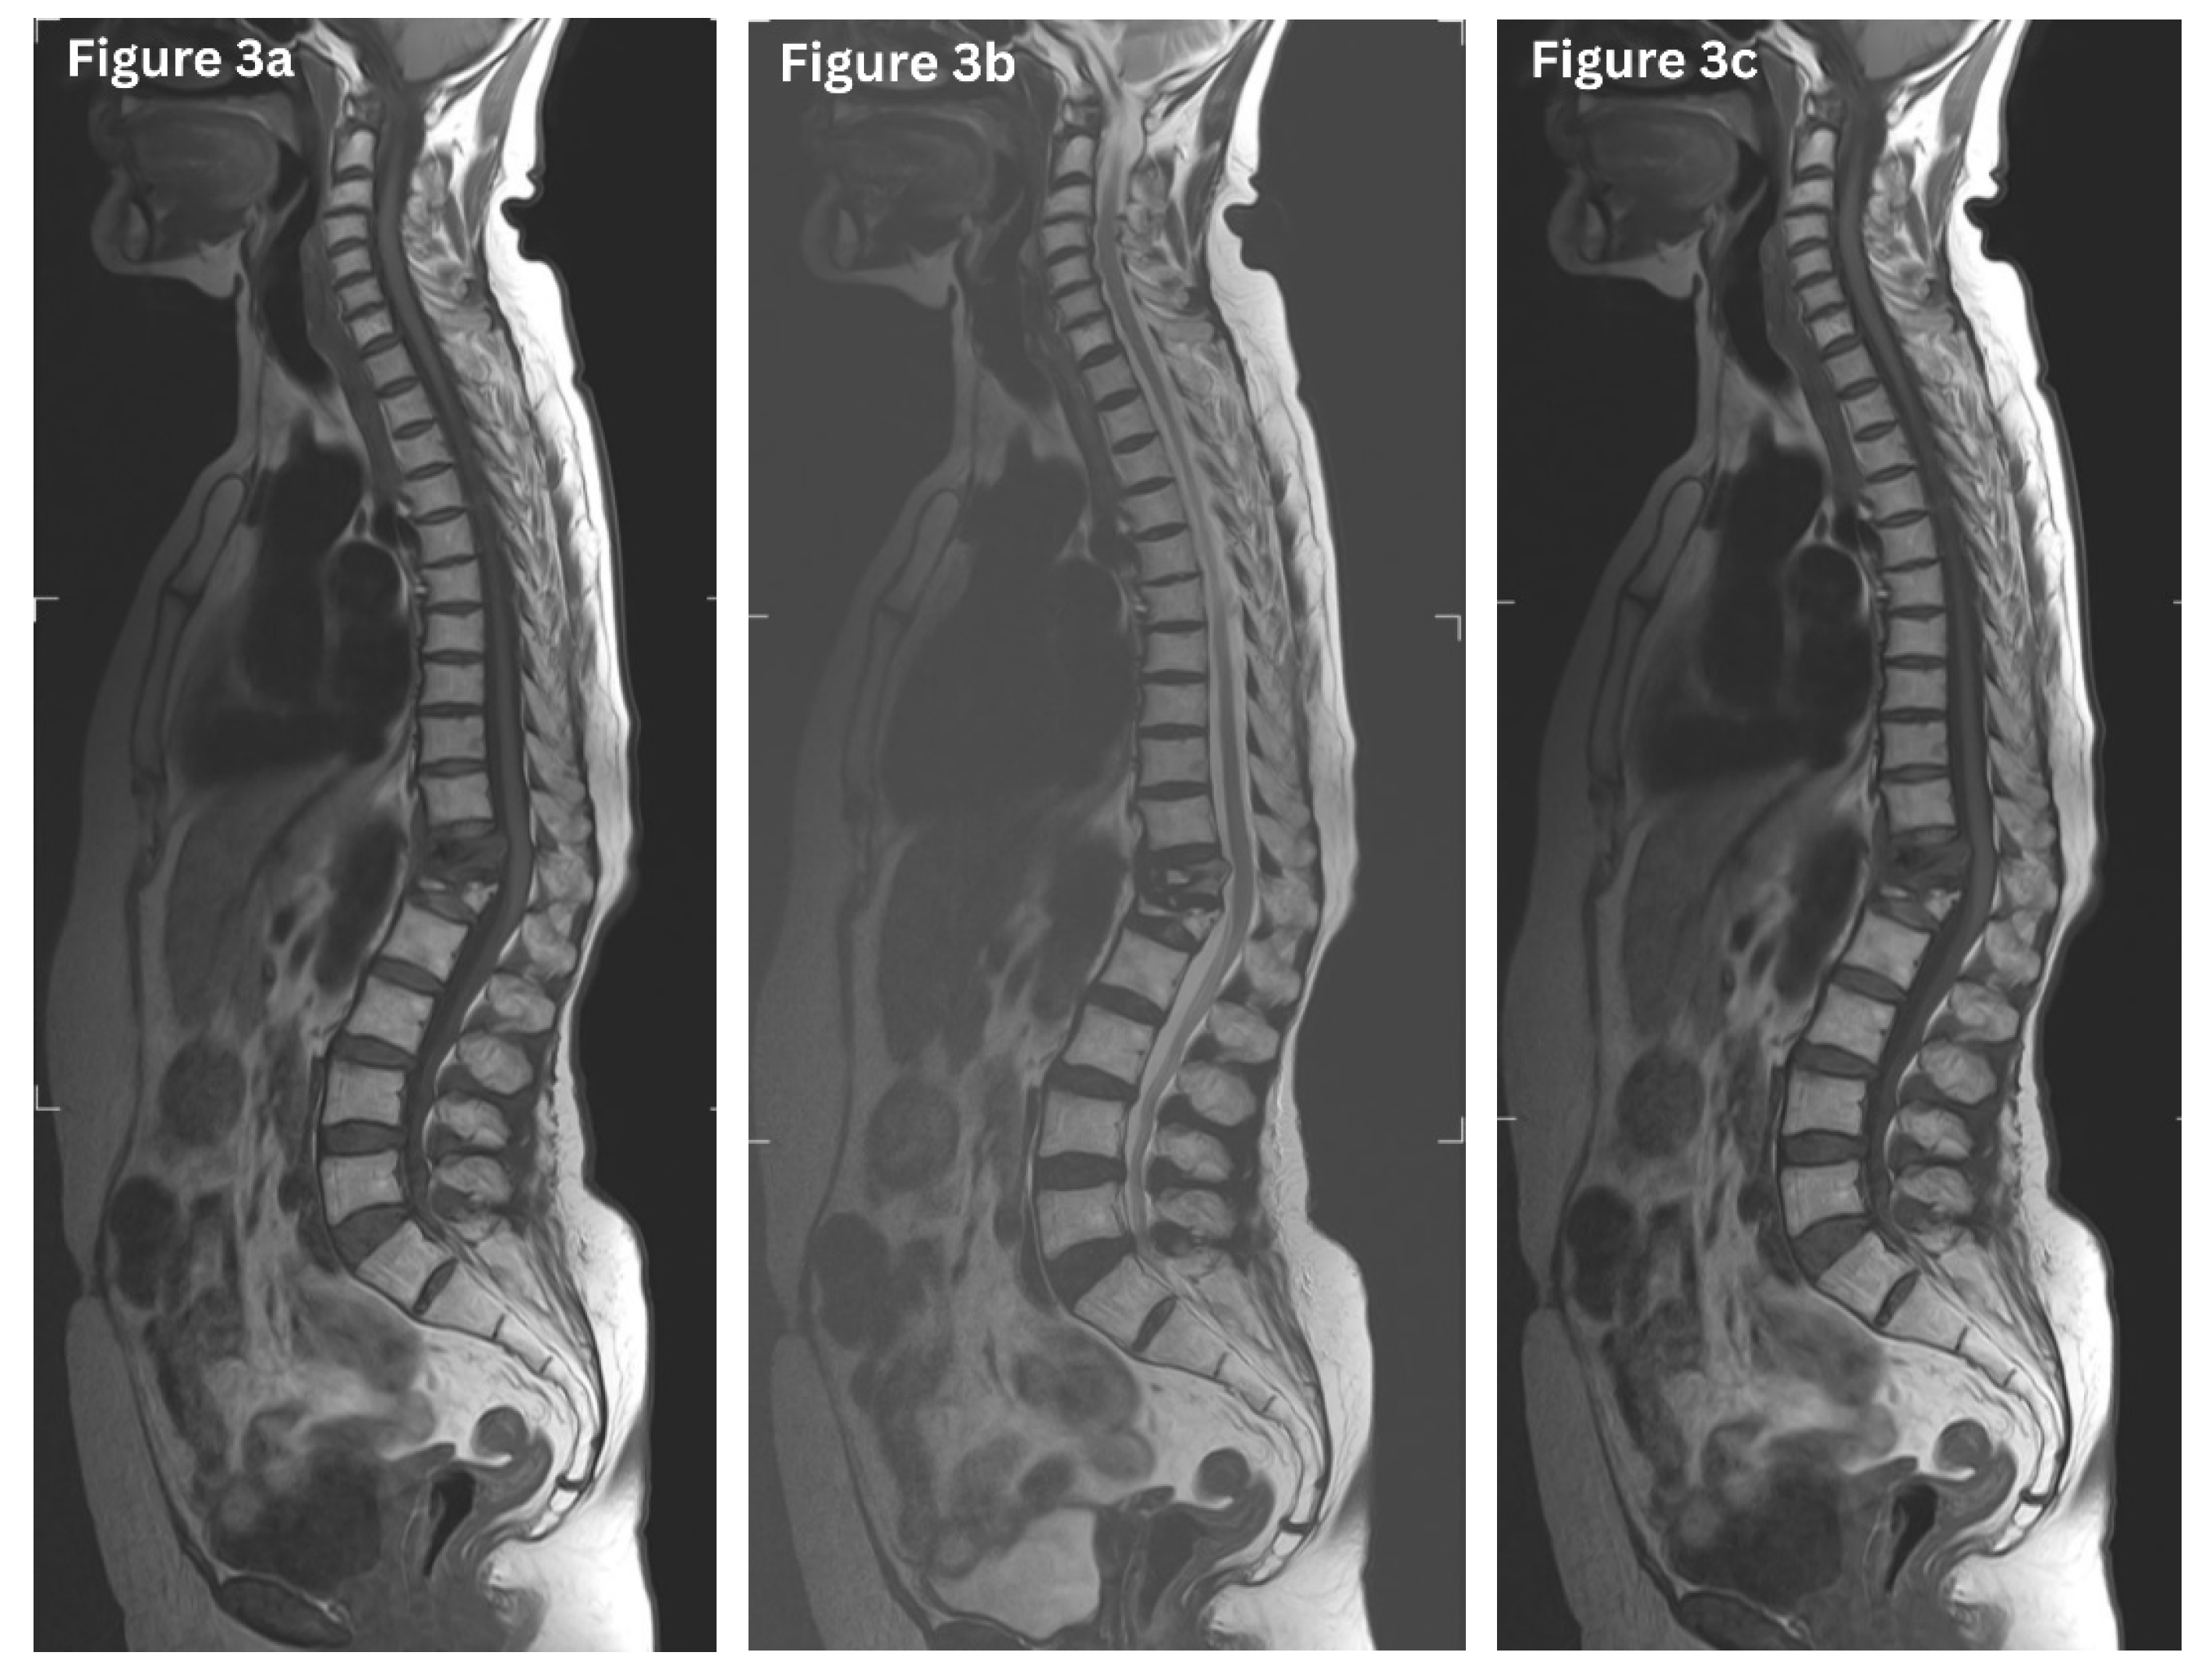

CT offers excellent spatial resolution for evaluating fracture morphology, cortical breaches, retropulsed bone fragments, posterior element involvement, and neural canal involvement. In osteoporotic compression fractures, CT typically reveals anterior wedge-shaped vertebral bodies with intact posterior elements and absence of soft-tissue mass. Conversely, malignant fractures may show lytic lesions, cortical destruction, irregular endplates, and associated paraspinal or epidural soft-tissue masses (Figure 2). CT is also invaluable in surgical planning and evaluating complex burst or unstable fractures. [9,11]

Figure 2. Sagittal CT image of the thoracic spine (bone window) demonstrates markedly reduced bone mineral density with multiple lytic vertebral lesions. There are associated multiple severe compression fractures involving the upper thoracic vertebrae, resulting in loss of vertebral body height and kyphotic deformity, features suspicious for an underlying pathological process.